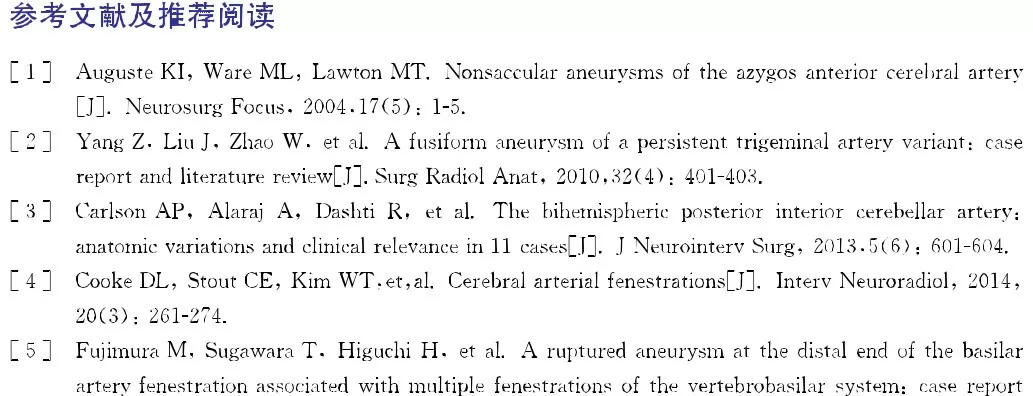

CT:头颅CT提示蛛网膜下腔出血,出血位于鞍上池、环池及侧裂池,双侧对称,无脑实质出血及脑积水表现,Fisher:分级2级(图18-1A)。

A:术前头颅CT;

图18-1变异原始三叉动脉动脉瘤患者术前CT及DSA影像